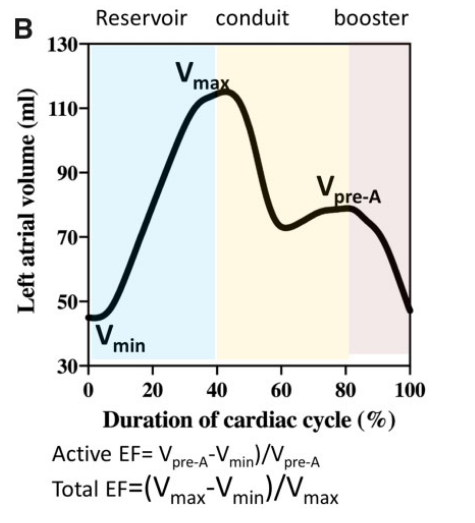

Left atrial function has been typically divided into three integrated phases: reservoir, conduit and booster-pump (Figure 1) [7–10]. Reservoir: an expansion phase during left ventricular (LV) systole; the LA stores pulmonary venous return during LV contraction and isovolumic relaxation. Conduit: the LA transfers blood passively into the LV during ventricular diastole. Booster-pump: contractile component (when supraventricular rhythm is present);